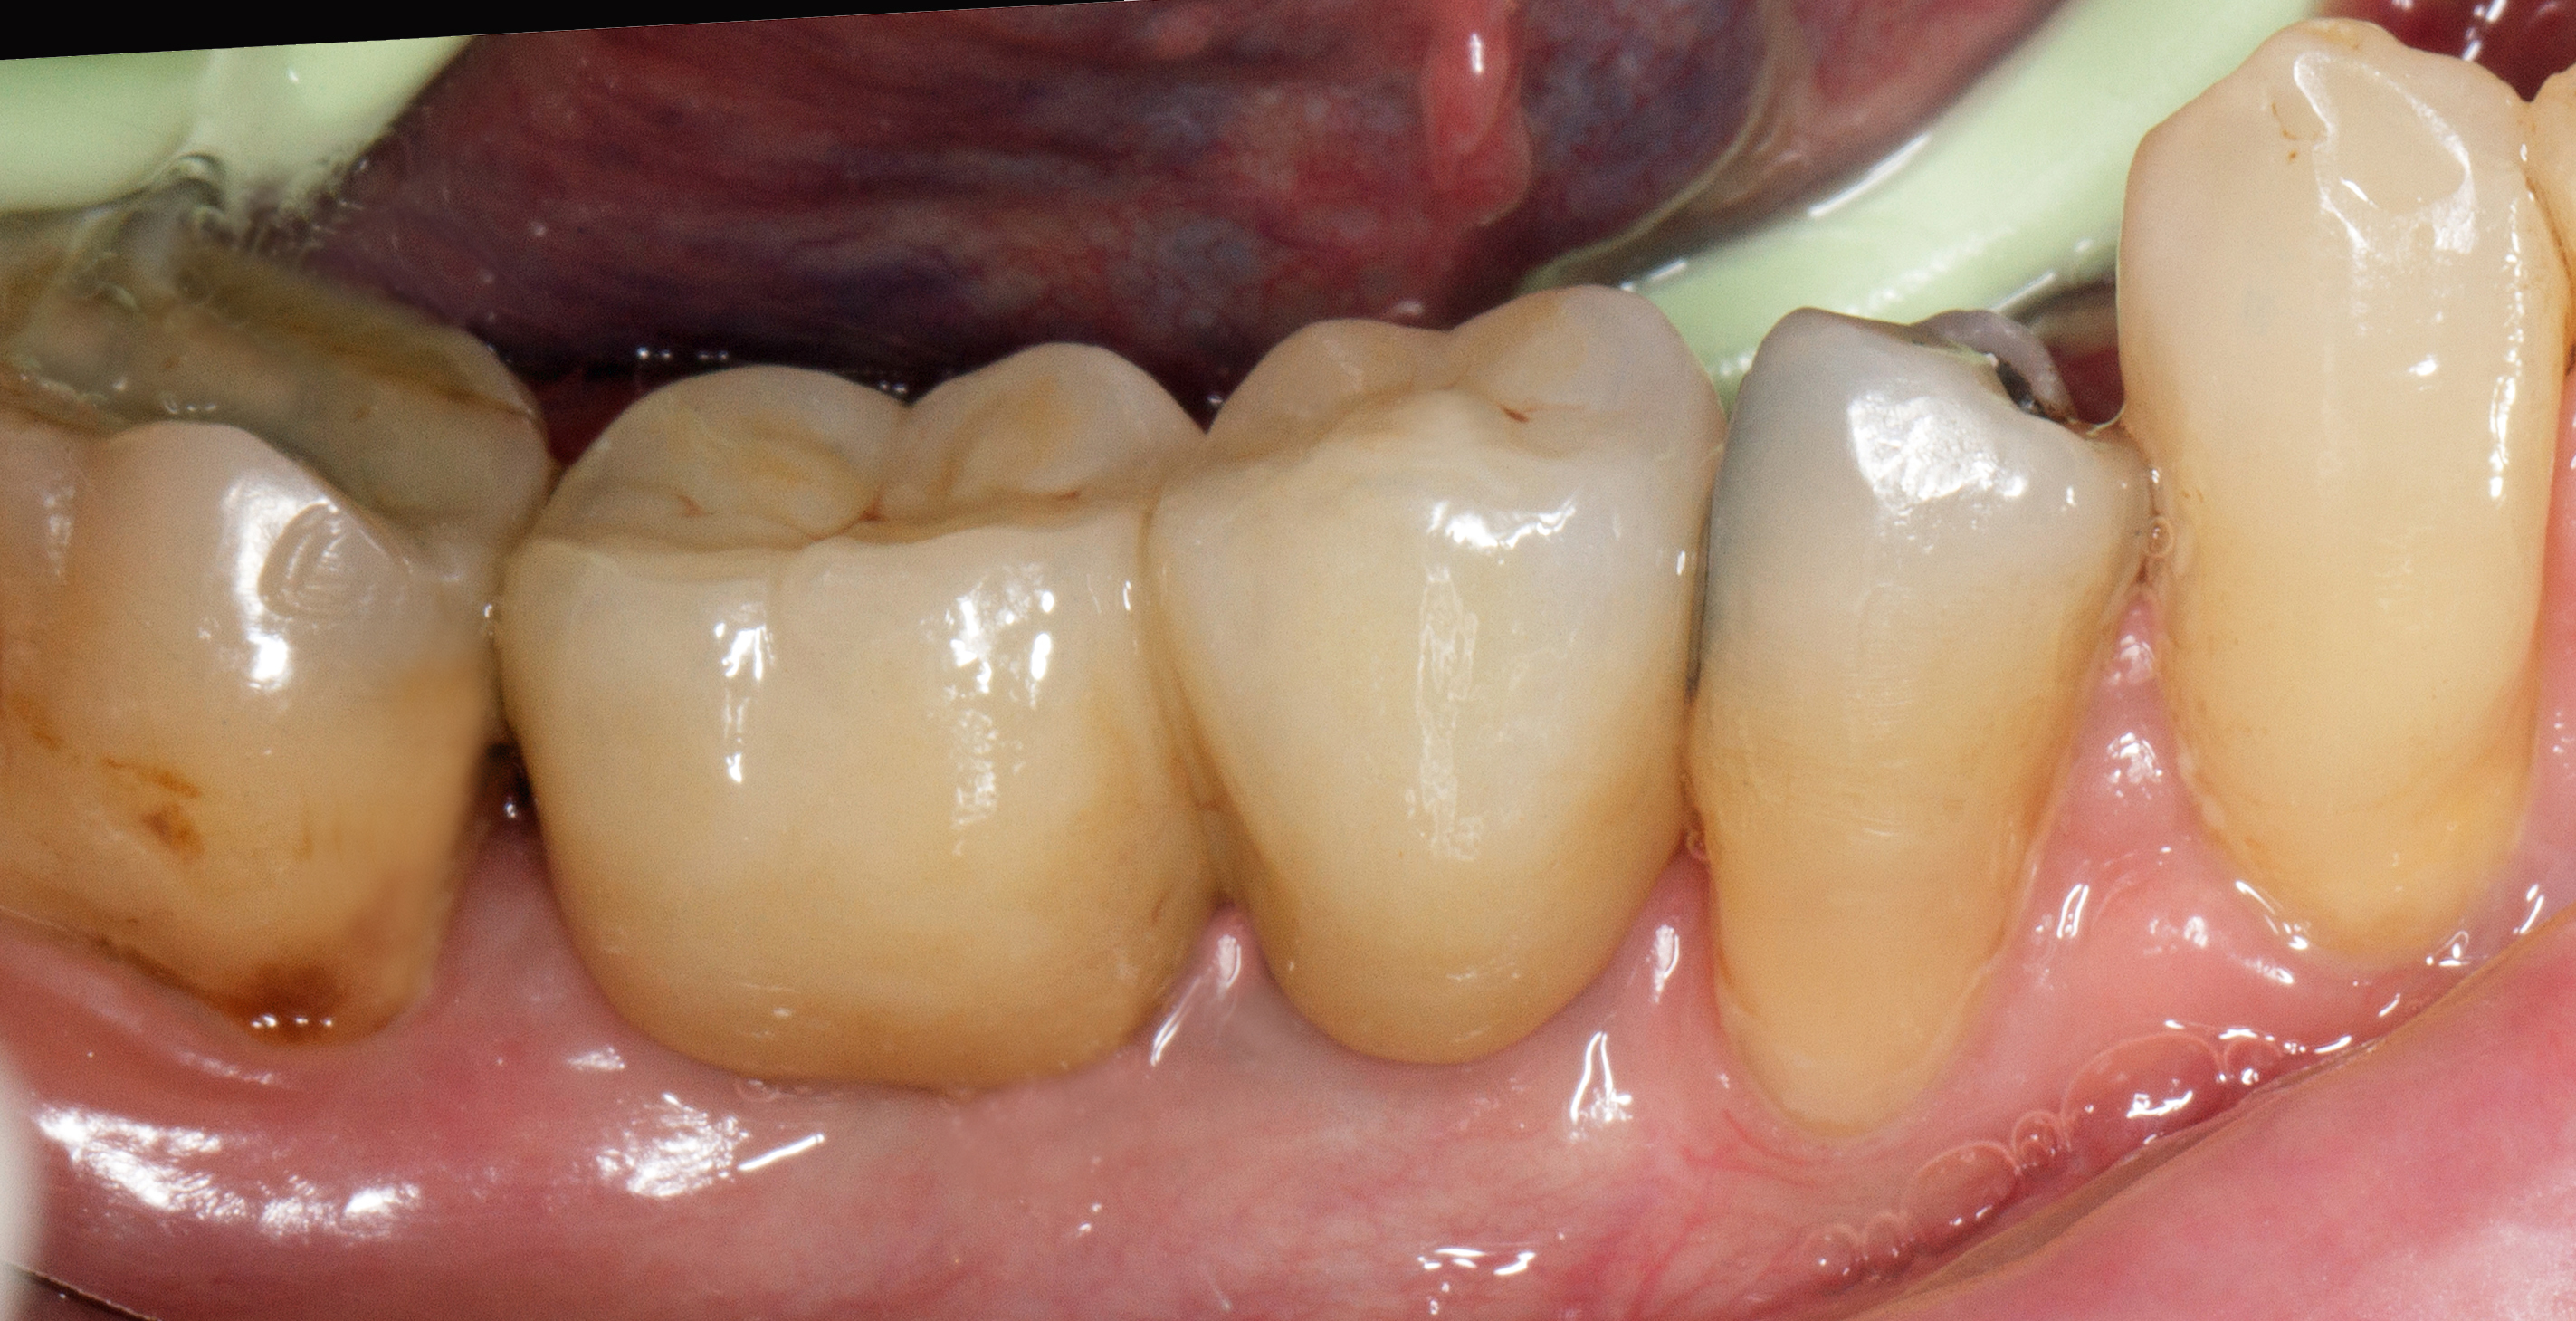

Dopo ulteriori quattro mesi si può procedere con l’ultima fase chirurgica di scopertura delle due fixture e di inserimento di abutment definitivi personalizzati.

Dopo l’apertura del lembo di accesso si evidenzia tessuto osseo corticalizzato anche nella zona vestibolare e crestale di 4.5. La visione occlusale consente di apprezzare la ricrescita ossea coronale alla vite tappo della fixture in 4.5 e del tessuto osseo vestibolare rispetto al bone housing. La misurazione ISQ di 4.5 restituisce l’alto valore di 86 (Figure 23-24).

Vengono inseriti due abutment protesici in titanio personalizzati con tecnica di preparazione verticale e una matrice eterologa di natura dermica (Osteobiol® Derma 2 mm) viene inserita a ponte sui due abutment per consentire di avere maggior tessuto cheratinizzato perimplantare. La sutura a punti staccati lascerà guarire una parte della matrice dermica per seconda intenzione (Figure 25-26).

Dopo circa sei settimane si è formata una ampia banda di tessuto cheratinizzato perimplantare che facilita una adeguata igiene orale e da protezione al tessuto osseo sottostante (Figure 27-28).

Vengono cementate due corone in zirconio stratificato (Figura 29). Il controllo clinico e radiografico dopo 18 mesi mostra la buona risposta dei tessuti gengivali e la stabilità ossea perimplantare (Figure 30-31).